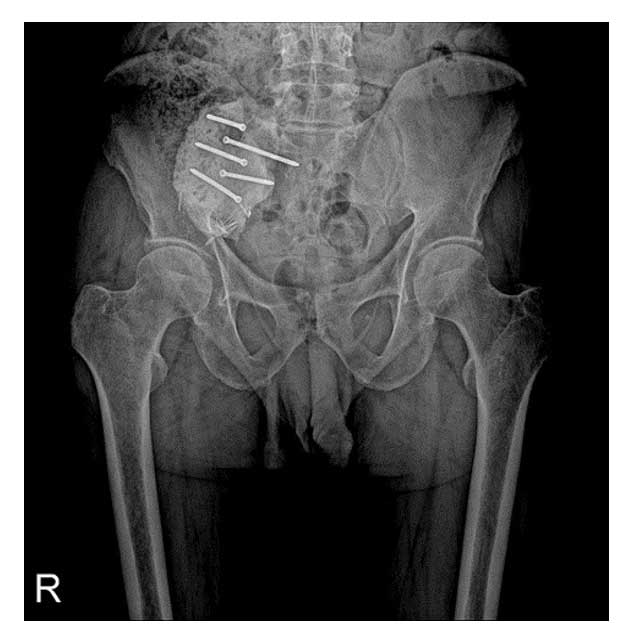

Tümörlü doku cerrahi olarak çıkarıldı. Oluşan boşluk kemik çimentosu (PMMA) ile dolduruldu ve bölge vidalarla güçlendirilerek stabilizasyon sağlandı.

Ameliyat Sonrası: Sağ sakroiliak eklemde vidalar ile tutturulmuş kemik çimentosu.